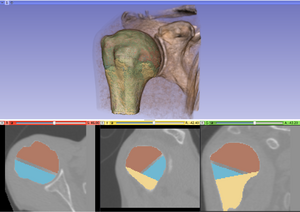

Tutorial and description of panelsUsing the first tab of the loadable module the user should provide the following input data: -3D CT image(volume) of non fractured bone (='Reference image') After providing the input data the 'Initialize reconstruction'-button should be pressed in order to create 3D models of the labelmaps and initialize the reconstruction process If the user wants to provide a better manual interaction the transform sliders (from within the fracture reconstruction) module can be used. Better initialization will decrease the calculation times for the subsequent alignment process and potentially lead to better results. The "Reset manual transform" button to reset the postion of each fragment to the state prior to the manual interaction. After the initialization process is finished the second tab will be opened. The 2D and 3D views will be updated and a surface rendering of the fragments and reference bone will be provided. The user can change colors, opacity and visibility for each single fragment.

After the first step of the reconstruction is finished and user can inspect the intermediate result. 2D and 3D views will be update according to the calculated transformations. At this point the user, the following scenarios are possible: 1) Good registration - Accept registration without performing further registration (fine tuning part will be skipped). By pressing the "Start fine tuning" button the second part of the reconstruction process in which the fragments will be aligned against each other (without using the reference bone) will be started. The parameters for this step can be changed in the corresponding parameter tab ("Parameters for fine tuning") After the calculations for the fine tuning step are finished, the last tab will be opened ("Result step 2"). Again 2D and 3D views will be updated accordingly and the same 4 scenarios as in the previous step are possible.  Updated 2D and 3D views after final step of reconstruction. Note that the visible gaps are due to missing bone that has been "simulated" in this (toy) example. This view was generated using a wireframe representatioin of the fragments in combination with a volume rendering of CT dataset of the (healthy) reference bone